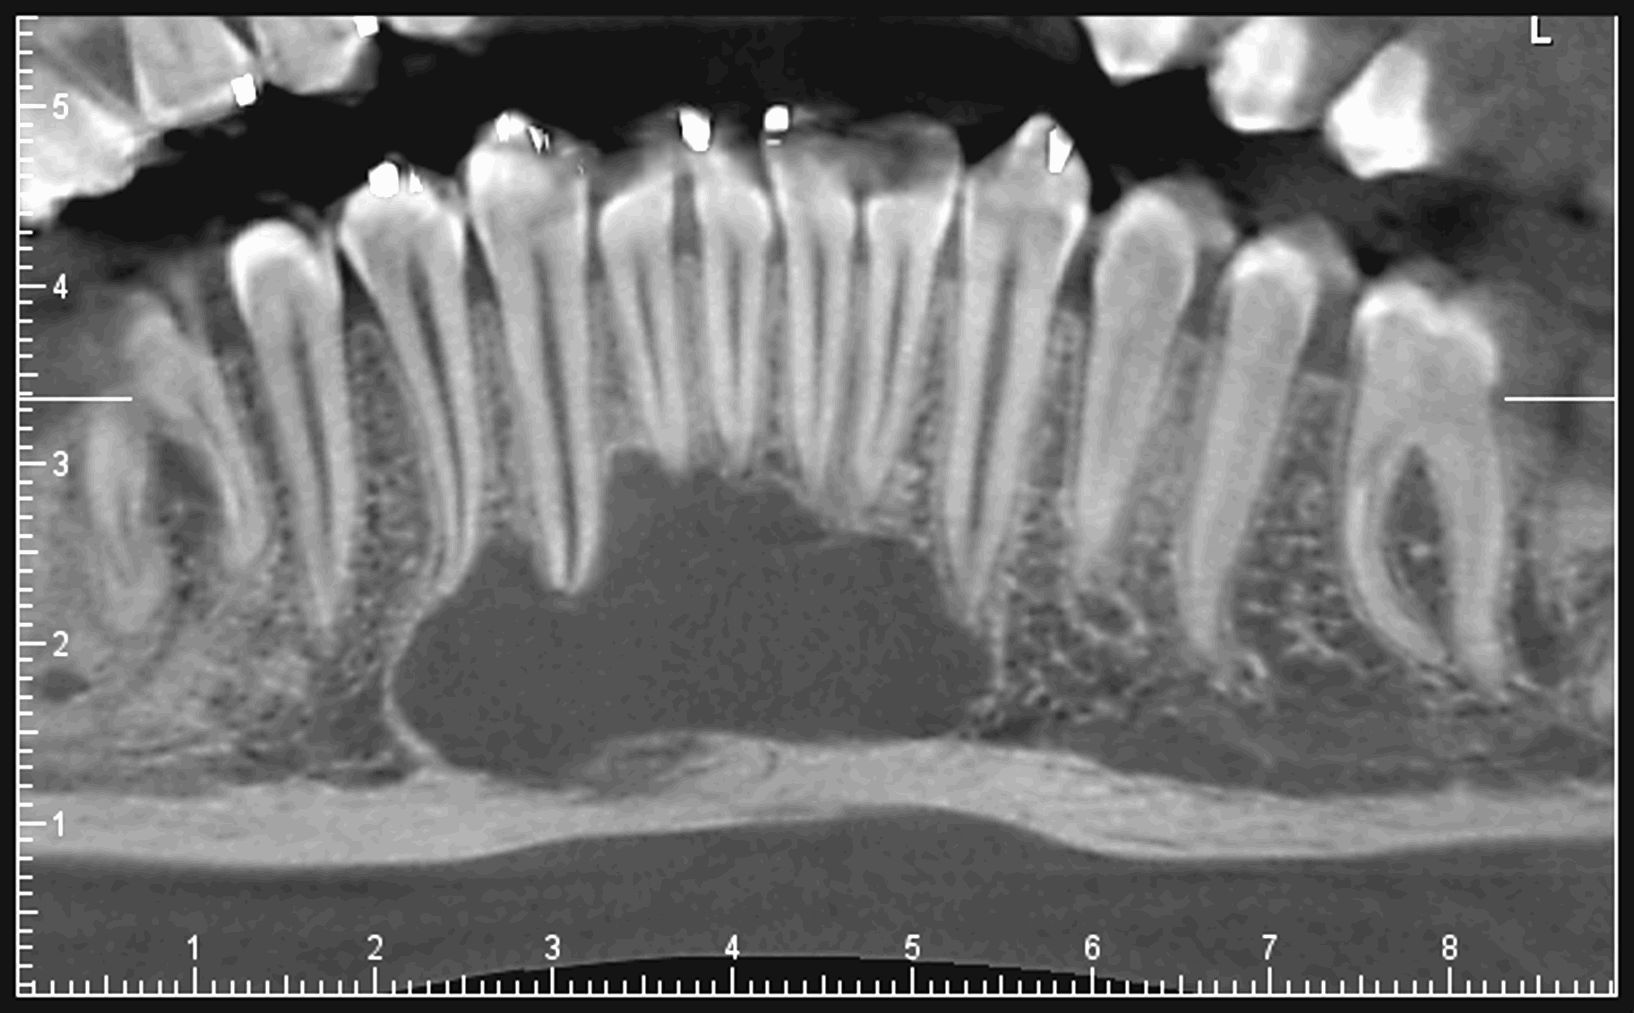

Le cone beam est une nouvelle technique de radiographie numérisée situé entre le panoramique dentaire et le scanner, il utilise un faisceau d’irradiation de forme conique d'où son nom. Cet appareil présente notamment l’avantage d’être plus précis que le panoramique dentaire et il possède une résolution similaire, voire supérieure à celle du scanner, avec en plus la possibilité d’une reconstruction numérique en 3D.

Il permet de balayer en un seul passage l’ensemble du volume à radiographier et en étant moins irradiant que le scanner.

Le cone beam utilisé en pathologie dentaire et maxillo-faciale est indiqué pour l’examen des tissus minéralisés (dents, cartilages, os), il permet d’identifier les lésions osseuses, les fractures, les infections, les kystes ou les corps étrangers.

Les nouvelles générations de scanner permettent de faire une acquisition d’un volume global d’une partie du corps et de travailler à l’intérieur de ce volume en isolant une structure anatomique donnée et de l’explorer dans tous les plans de l’espace.

Grace à la technique de seuillage il est possible de dissocier progressivement les dents des structures osseuses environnantes dans le volume donné.